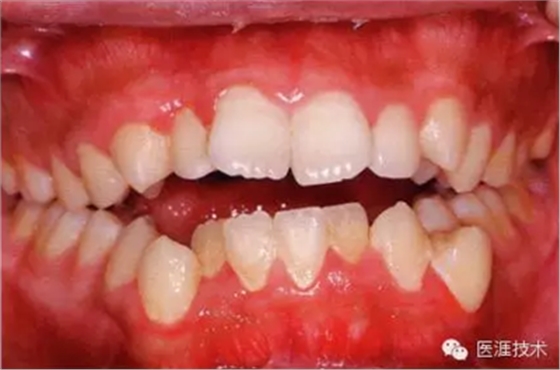

健康且正常的牙周組織臨床圖像

50歲女性的健康口腔內(nèi)部

圖為50歲女性,無特殊全身疾病,不抽煙。持續(xù)保養(yǎng)6年。無填充物等問題,依照患者本人要求持續(xù)觀察。牙周組織臉頰側(cè)雖見部分萎縮,但X線牙片顯示牙間無骨吸收現(xiàn)象,保持著比較健康的狀態(tài)。